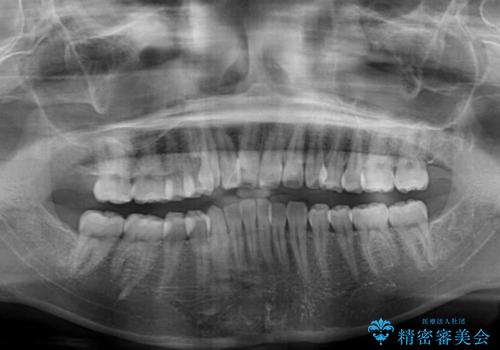

非抜歯矯正ではデコボコを解消することでより口元が突出する可能性があるため、上顎右右側の小臼歯1本の抜歯を行い、ワイヤー装置による矯正治療を行うこととしました。

正中位置を合わせるために、上顎臼歯部にアンカースクリューを埋入することとしました。